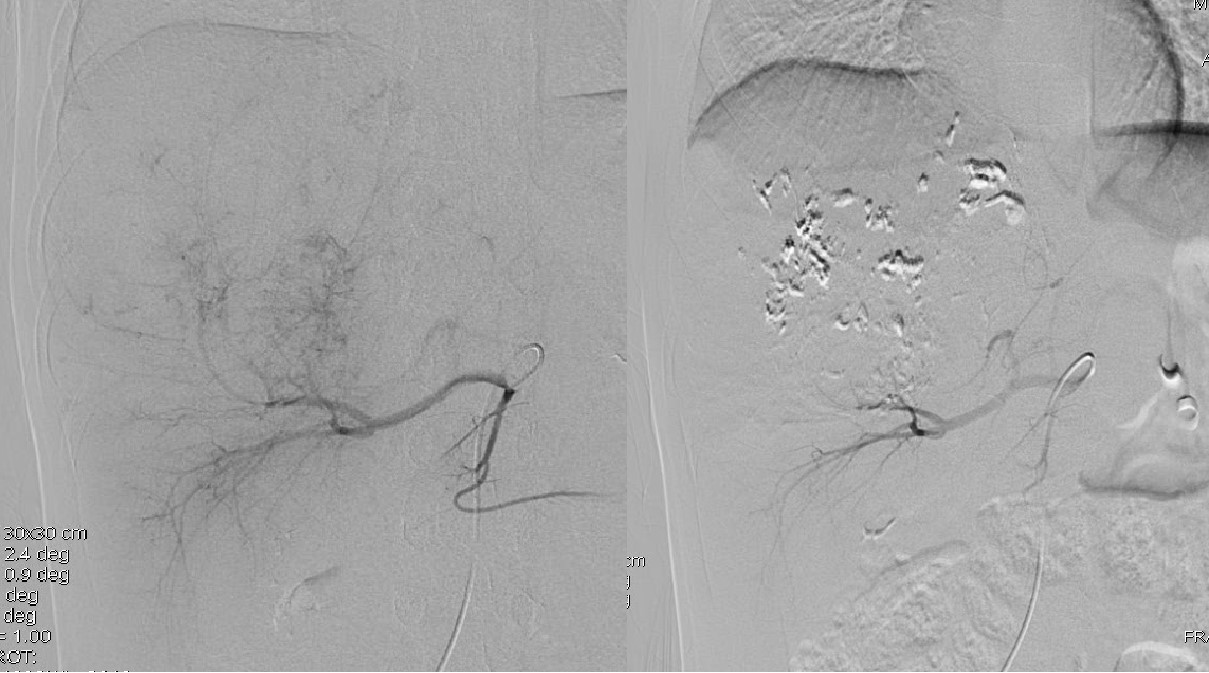

肾母细胞瘤又称为Wilms tumor,是儿童最常见的腹部恶性肿瘤,在文献上称谓此瘤的名称多达80余个,反应出对该肿瘤认识过程的复杂性,其发病率在小儿腹部肿瘤中占首位。肿瘤主要发生在生后最初5年内,特别多见于2~4岁。左右侧发病数相近,3%~10%为双侧发病,或同时或相继发病。男女性别几无差别,但多数报告中男性稍多余女性。随着对肾母细胞瘤组织病理学检查及DNA含量测定的研究,并根据临床分期与病理类型所制定的治疗方案,肾母细胞瘤的治疗效果取得了惊人的进步。经肾动脉化疗栓塞术已经成为肾母细胞瘤重要治疗方案,特别是对局部向外侵犯或跨过中线的肾母细胞瘤,已经得到了广泛的认可,其技术已趋于成熟。同时,经肾动脉的化疗栓塞术可激活机体免疫机制来对抗肿瘤。经肾动脉化疗栓塞术治疗肾母细胞瘤的优势:1、经肾动脉化疗栓塞治疗肾母细胞瘤,化疗栓塞药物通过肾动脉直接作用于瘤体,明显优于全身化疗。2、目前普遍认为肾动脉的完全栓塞相当于先结扎肾动静脉,不仅可以减少肿瘤播散,而且由于阻断了肿瘤血供,可以造成肿瘤缺血坏死萎缩,病肾因梗死而水肿,与健康组织层次分明,曲张的肿瘤血管塌陷。3、对于巨大肾母细胞瘤,经肾动脉化疗栓塞后,瘤体明显缩小,可达80%以上。